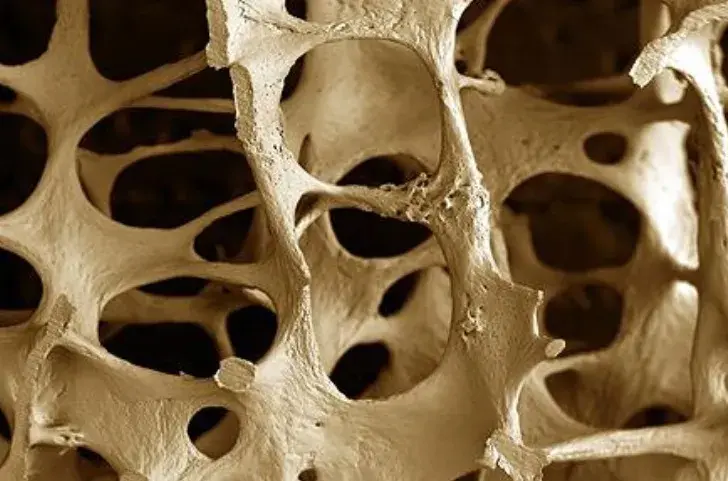

Fadiga na DRC: Como identificar e tratar?

Fadiga na DRC: Como identificar e tratar?